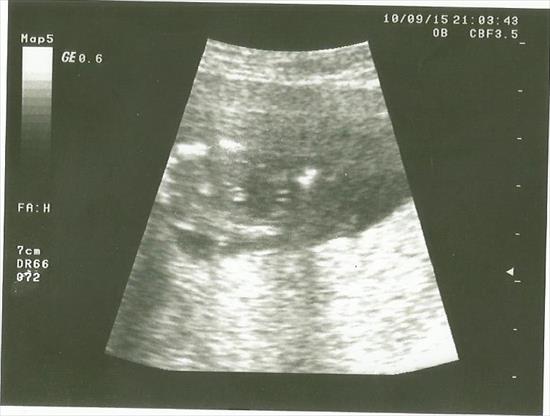

here is my ultrasound 14 weeks 5 days, can you tell me what it looks like ?my doctor will tell me for sure next week.Attachment 27418

Looks like a girly 'hamburger' to me! Congrats!

Looks similar to my second boy

So hard to tell, but if I had to guess I'd say it's leaning girly.

This one is tricky. I have a similar pic from my 3rd at 15 weeks and hes a boy.